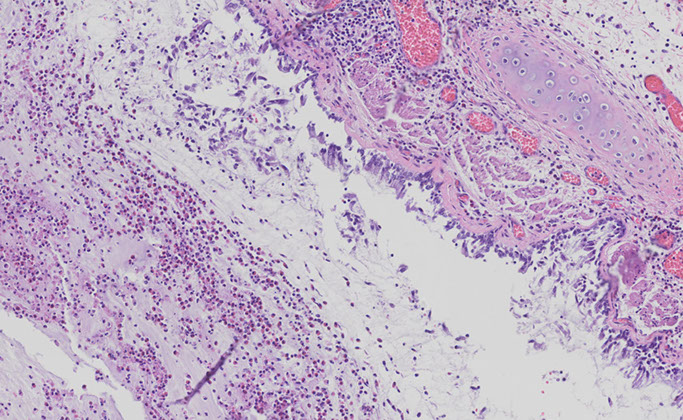

Bronchiolitis Obliterans-Organizing Pneumonia (BOOP)

- aka Organizing Pneumonia (OP)

Airspace-filling, active fibrosing process involving the distal bronchioles, alveolar ducts and alveoli in varying proportions, commonly seen c aspiration

- clinically has Restrictive PFT results

- subacute onsetand some pts have hx pf recent RTI

- assoc c infx, rx (gold, bleomycin, inhalers), rads, collagen vascular dz, eosinophilic / hypersensitivity/ nonspecific interstitial pneumonia

Micro: fibroblastic plugs ("Masson bodies") that fill air spaces that are elongated, lots of foamy macros

- appears patchy on low power

DDx: interstitial pneumonia, which have temporal and spatial heterogeneity and is interstitial (rather than intraluminal), and are always assoc c architectural distortion in form of scarring and honeycomb lesions

Px: very good (unless steroids don't work)

BOOP